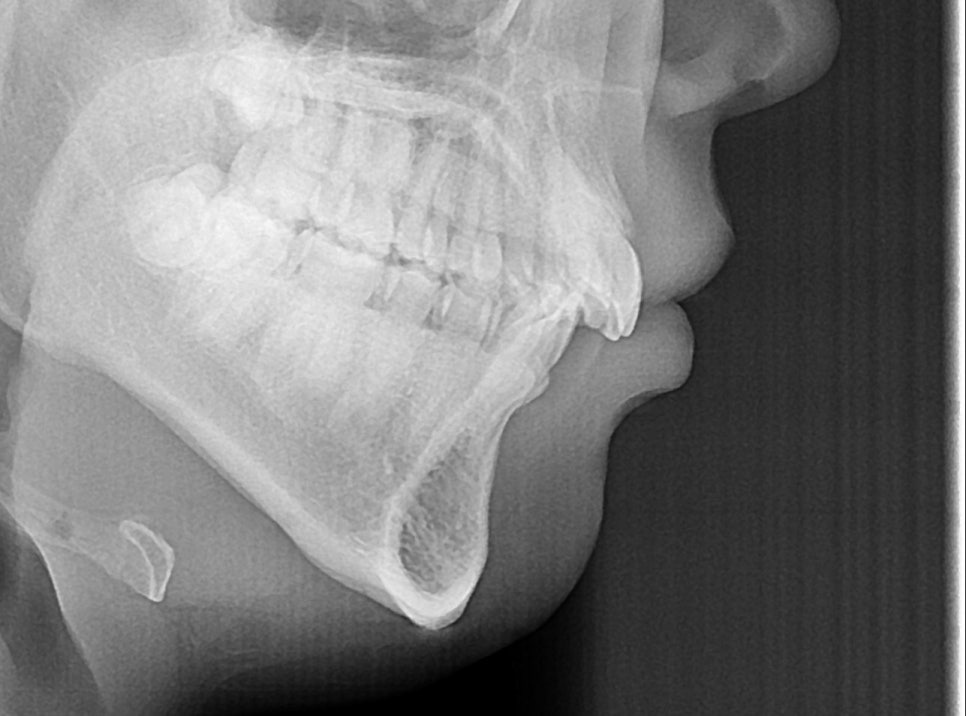

이번 내용과 별개로 치아 문제를 넘어서

턱 크기 차이가 심할 경우에는

과개교합 교정만으로 해결이 되지 않습니다.

그땐 양악이나 하악 전진술과 같은

수술이 권해질 수 있으므로

의료 전문가와 면밀한 상담이 필요합니다.